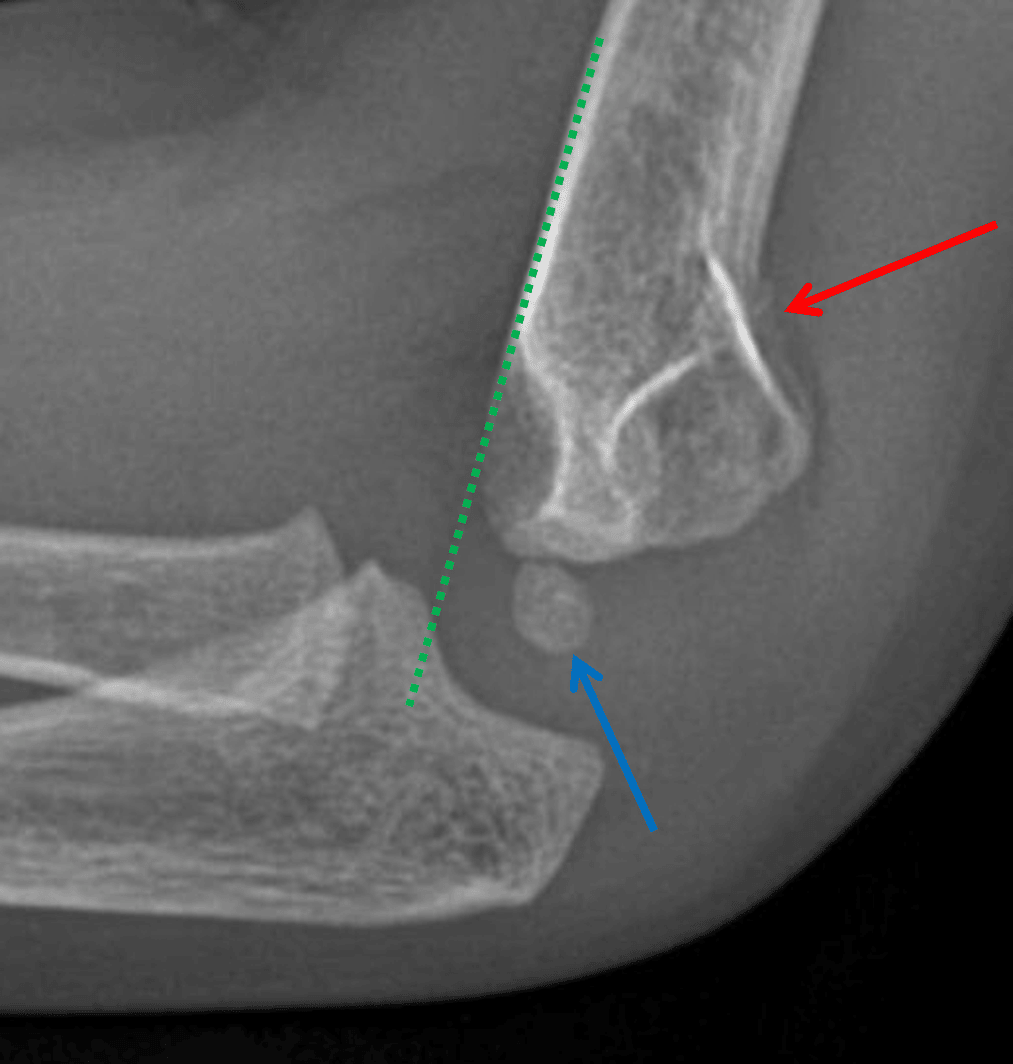

Anterior offset of the anterior humeral line (green dotted line) relative to the capitellum (blue arrow). Acute supracondylar fracture with mild posterior angulation (red arrow).

- Look for anterior offset of the anterior humeral line (should intersect the middle third of the capitellum, but in the case of supracondylar fracture will intersect the anterior aspect or may miss the capitellum entirely), which may be the only sign of a fracture